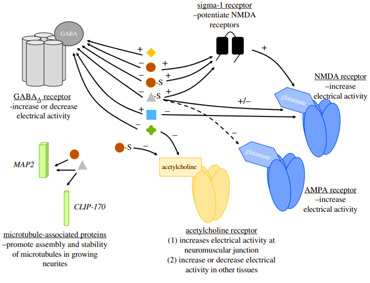

James Mouton and Renee Duckworth integrate advances in developmental neurobiology and psychiatric pharmacology to show that maternal steroid metabolites have direct neuro-modulatory effects and shape the development of neural circuitry of crucial behavioural traits.